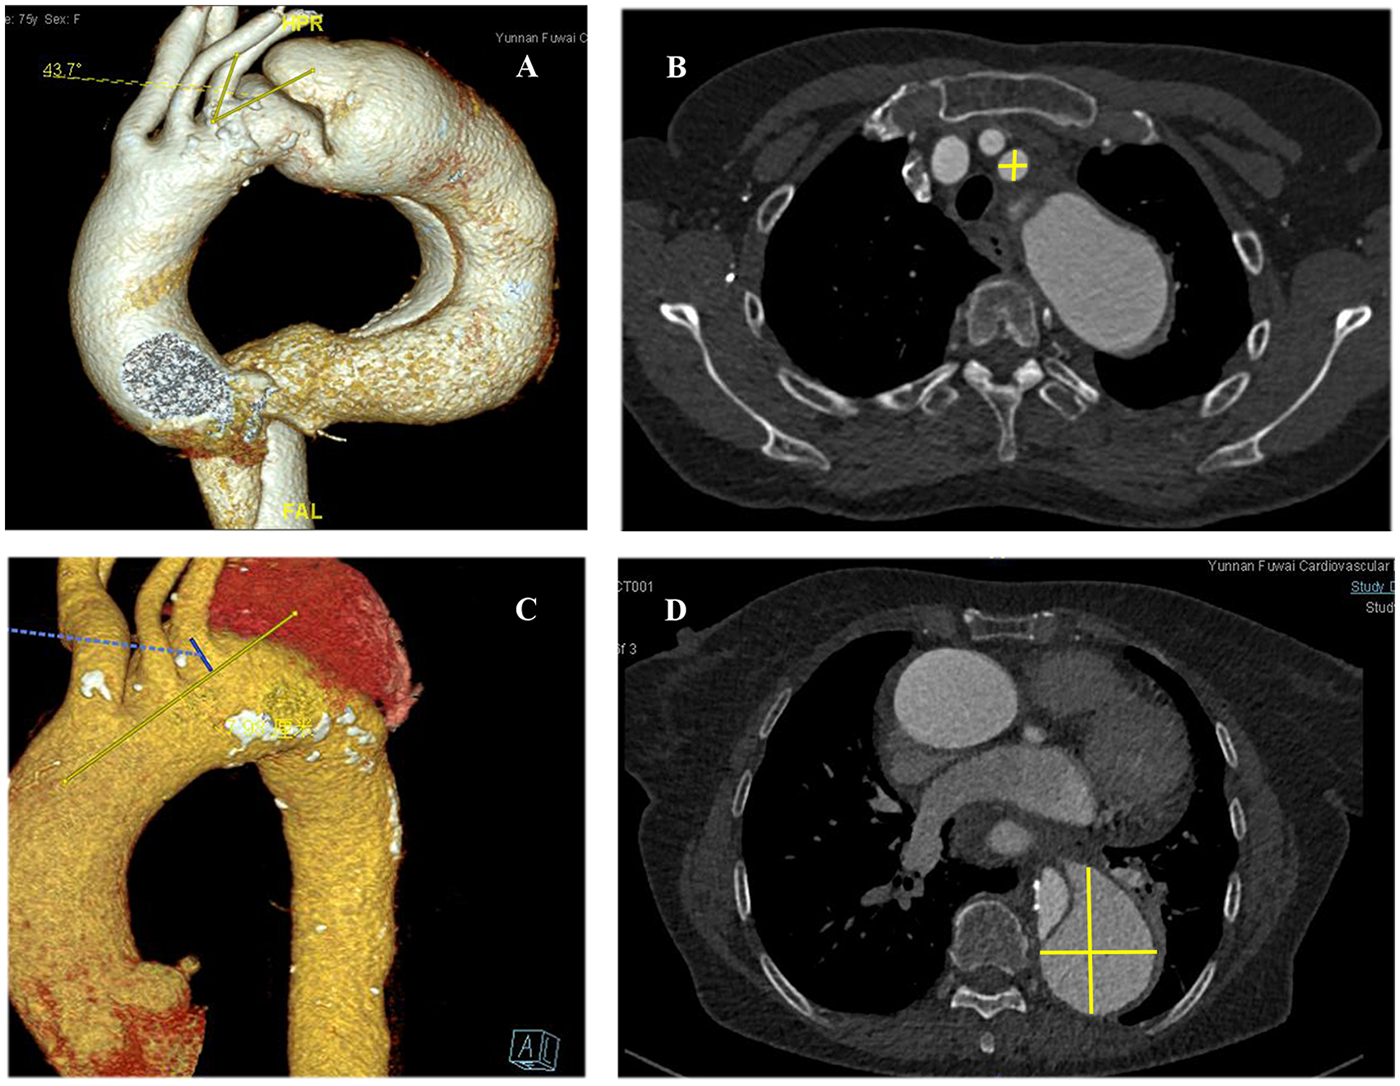

We measured and analyzed the proximal opening angle of the LSA and its diameter, the distance between the LSA and the aortic arch in the coronal section, and the aortic aneurysms in T1EL/T2EL patients. Univariate and multivariate logistic regression analyses showed that the proximal opening angle of the LSA (OR 3.141, 95% CI: 2.615–3.773; P < 0.001) was significantly associated with the incidence of T1ELs, as observed in CTA images (Figure 2A and Table 4).

Figure 2

High-risk factors for type I or type II endoleaks as shown by computed tomography angiography of the aorta. (A) Proximal opening angle of the LSA (yellow lines) on the first preoperative view. (B) Diameter of the LSA (yellow crossed lines). (C) Distance (blue line) between the LSA and the aortic arch in the coronal section (yellow line). (D) Maximal diameter of the aorta (yellow crossed lines).

Univariate and multivariate logistic regression analyses indicated that the proximal opening angle of the LSA (OR 1.168; 95% CI: 0.222–6.152; P < 0.001) and the diameter of the LSA (OR 2.663; 95% CI: 2.266–3.13; P < 0.001) were significantly associated with the occurrence of T2ELs (Figures 2A,B, Table 5).